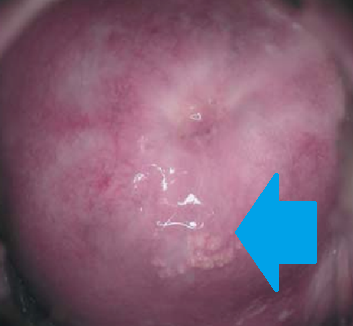

Gross examination of the excised cyst reveals a smooth surface lining of uniform thickness without papillary projections (Courtesy Dr. V. Penopoulos)